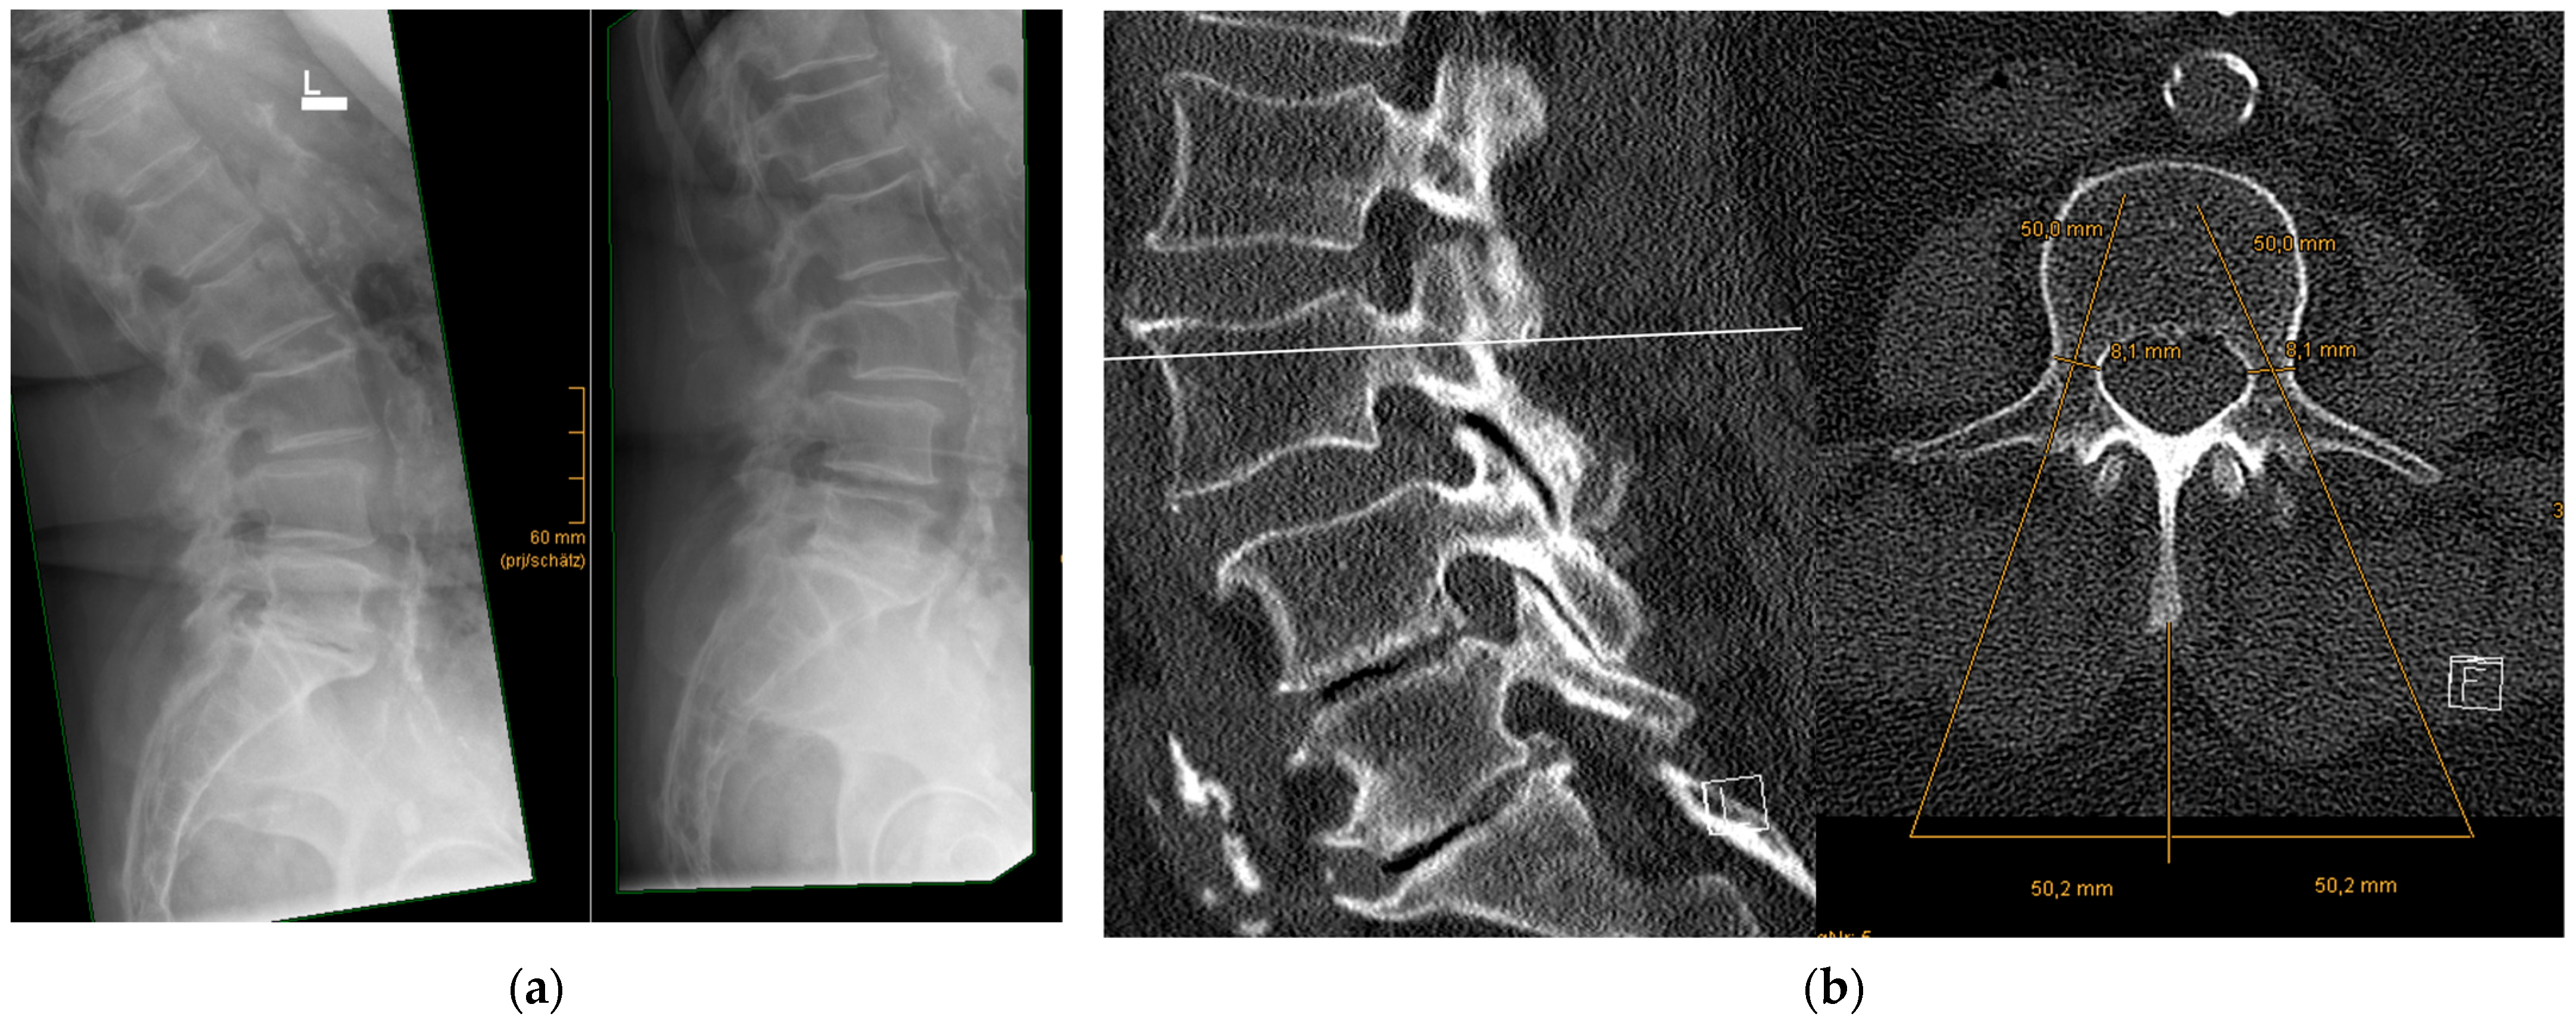

- Precise preoperative planning of screw trajectories and screw dimensions